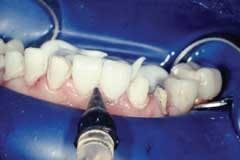

Seating the central incisors first, the teeth are etched with Scotchbond™ 35 percent phosphoric etchant for 10 seconds (Fig. 7), rinsed, and lightly dried, leaving the dentin moist.

If adjacent proximal surface is near or in contact, cover with small strips of Dead Soft Matrix (Denmat) to prevent from etching the surface. Two coats of Adper Single Bond Plus Adhesive are applied, thinned out, and left unpolymerized.

The resin cement is placed inside the veneers, and they are seated onto the preparations. With the smallest diameter tip (2mm) and the Optilux 501 Curing Light (Kerr), the veneers are tacked for five seconds in the middle third. Avoid polymerization of the margins or the cleanup of excess cement will become more time-consuming. Using a rubber-tip stimulator, microbrushes, and Glide dental floss, remove excess cement along the margins (Fig. 8).

The placement of a glycerin gel such as Oxygone™ (Cosmedent) along the entire margin will eliminate the oxygen-inhibited layer during polymerization. With a large diameter tip and the Optilux 501 Curing Light, each surface is polymerized for 40 seconds.